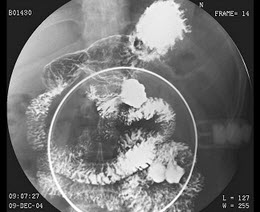

21、单项选择题

女,63岁,痰中带血2天,不咳嗽、发热,X线检查如图,最可能的诊断是()